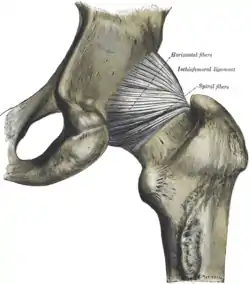

The extracapsular ligaments are the iliofemoral, ischiofemoral, and pubofemoral ligaments attached to the bones of the pelvis (the ilium, ischium, and pubis respectively). All three strengthen the capsule and prevent an excessive range of movement in the joint. Of these, the Y-shaped and twisted iliofemoral ligament is the strongest ligament in the human body. It has a tensile strength of 350 kg.[22] Iliofemoral ligament is a thickening of the anterior capsule extending from anterior inferior iliac spine to intertrochanteric line.[5] Ischiofemoral ligament is the thickening of posterior capsule of the hip and pubofemoral ligament is the thickening of the inferior capsule.[5] In the upright position, iliofemoral ligament prevents the trunk from falling backward without the need for muscular activity, thus preventing excessive hyperextension. In the sitting position, it becomes relaxed, thus permitting the pelvis to tilt backward into its sitting position. Ischiofemoral prevents excessive extension and the pubofemoral ligament prevents excess abduction and extension.[24]

Hip joint. Lateral view.

Hip joint. Lateral view. Hip joint. Lateral view.